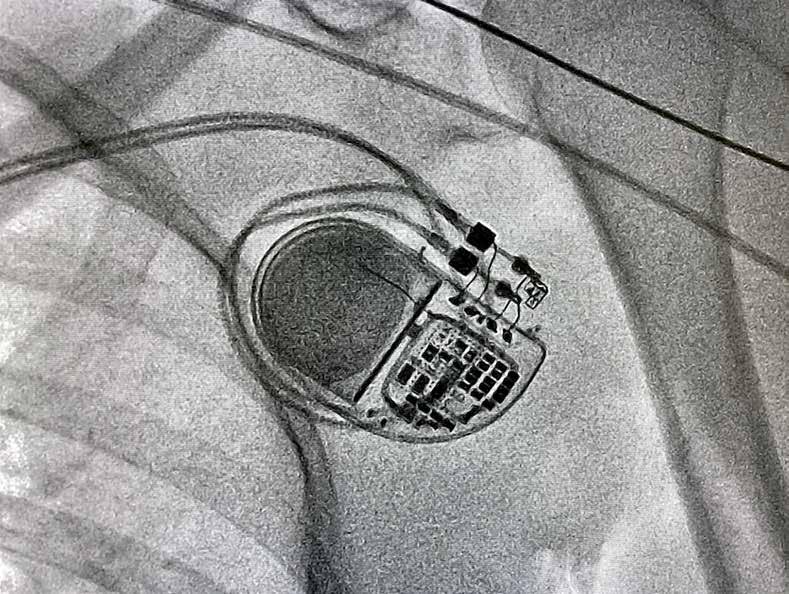

Karen Sandler heeft een groot hart. Letterlijk. “Mijn hartspier is zowat drie keer zo dik als gemiddeld, hypertrofische cardiomypathie heet dat. Ik voel me prima, maar het betekent wel dat ik een groot risico loop om plots een hartstilstand te krijgen en te overlijden.”

Daarom leeft Sandler met een ingeplante defibrillator die haar hart indien nodig weer aan de praat moet krijgen. “Eén van de eerste dingen die ik mijn arts vroeg, was: ‘Welke software zit hierin?’”